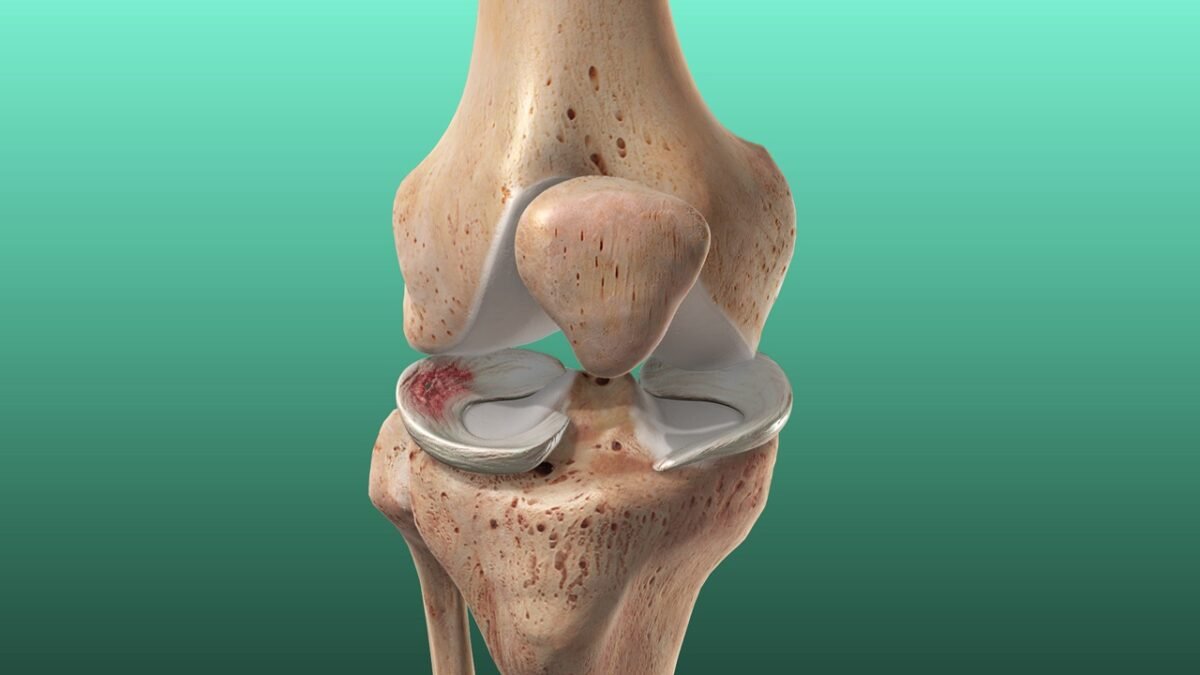

ما هو تآكل غضروف الركبة؟ ولماذا يُسبب خشونة الركبة؟

غضروف الركبة هو نسيج مرن يغطي أطراف العظام داخل المفصل، ويعمل كوسادة تمتص الصدمات وتسمح بالحركة السلسة.

عند حدوث تآكل غضروف الركبة تدريجيًا، تقل سماكته وتفقد الركبة قدرتها على الحركة الطبيعية، ما يؤدي إلى احتكاك العظام ببعضها، وهنا تظهر خشونة الركبة بكل أعراضها.

إذًا خشونة الركبة هي النتيجة المباشرة لتآكل غضروف الركبة، وليستا حالتين منفصلتين.

درجات خشونة الركبة

خشونة الركبة يمكن تقسيمها إلى عدة درجات بناءً على شدة الأعراض وتآكل الغضاريف، هذه الدرجات تساعد الأطباء في تحديد العلاج المناسب لكل حالة. إليكم تفصيل هذه الدرجات:

الدرجة الأولى

- ألم خفيف بعد المجهود

- تيبّس بسيط

- لا تظهر تغييرات واضحة في الأشعة

الدرجة الثانية

- زيادة الألم مع الحركة

- طقطقة في المفصل

- بداية ظهور نتوءات عظمية بالأشعة

الدرجه الثالثة

- ألم مستمر

- تورم واضح

- صعوبة في المشي والحركة

الدرجة الرابعة

- ألم شديد حتى أثناء الراحة

- فقدان كبير في الحركة

- تشوه في شكل المفصل

- تآكل شبه كامل أو كامل لغضروف الركبة